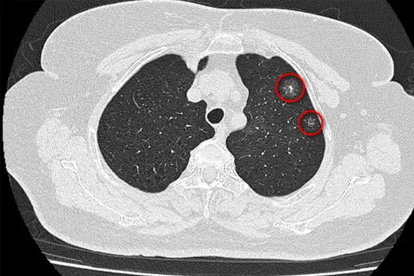

1、右肩持续性疼痛

肝脏和胆囊病变常会放射到右肩,特别是夜间加重的钝痛。有位患者当做肩周炎治疗半年,最后确诊肝癌时已经错过最佳治疗期。